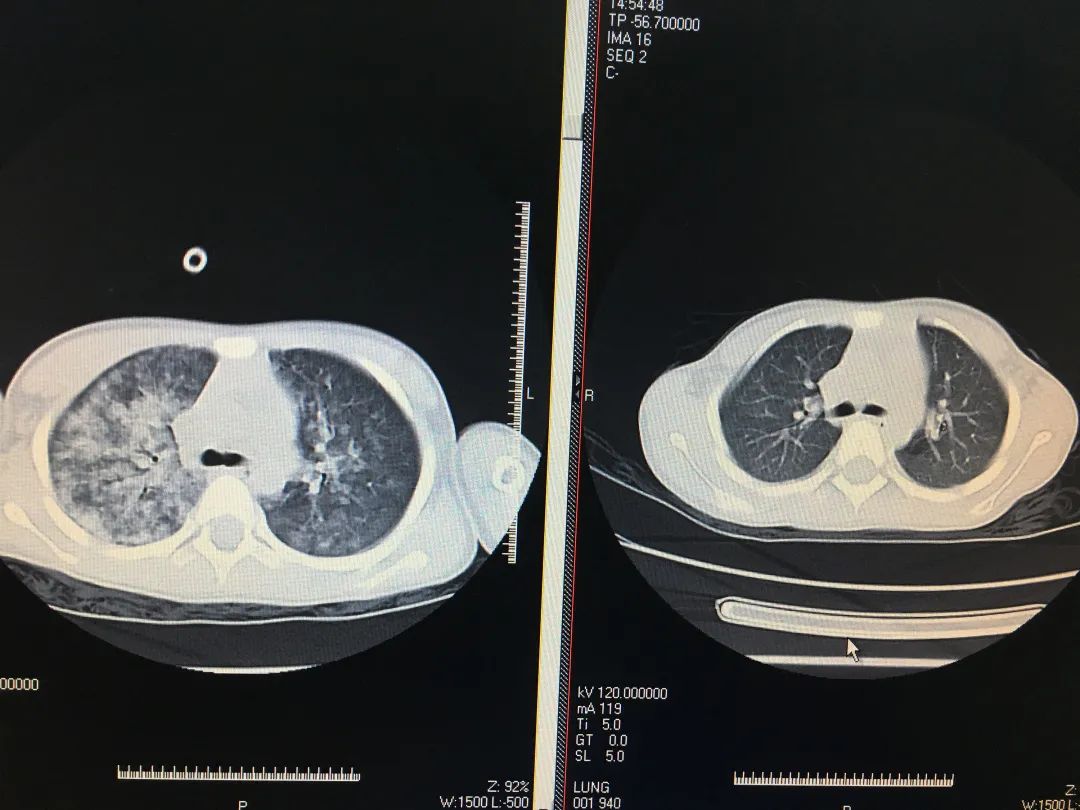

治疗前(左)后(右)对比

经胸部CT检查显示,发现小潘同学的双肺渗出明显,考虑有肺出血,小潘同学病情危急,医生与家属充分沟通并达成一致意见,给小潘同学进行了气管插管术,呼吸机辅助通气等一系列的抗休克抢救治疗,总算把小潘同学从鬼门关拉了回来。经过了为期一周左右的治疗,小潘同学终于在教师节前康复出院,开心地返校开学,与亲爱的老师和同学们团聚。